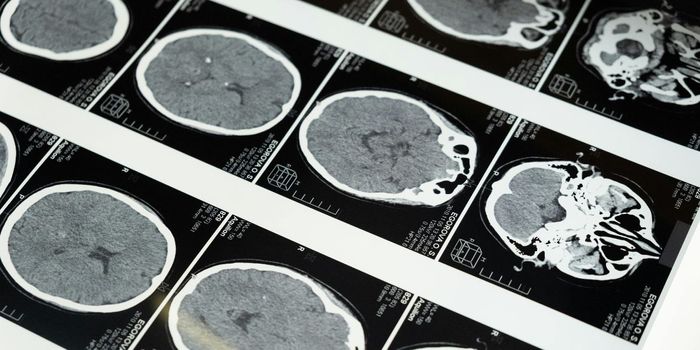

At the American Heart Association (AHA) Epidemiology/Lifestyle meeting, a team from Boston University Medical School presented data from the Framingham Heart Study finding that adults who exercised in mid-life had bigger-thus younger-looking--brains in later life, as much as 20 years later.

The BU team, led by Nicole Spartano, reviewed the records of more than 1,271 people (average age 41) who underwent MRIs at age 58. The team discovered that people whose hearts worked harder, or who had higher blood pressure, at the start of exercise in their 40's, showed about one year's worth of brain shrinkage one to two decades later. Brain shrinkage can be a sign of dementia, or simple brain aging.

The 1,271 participants were comprised of a subset of volunteers with the Framingham Offspring Study. The underwent exercise treadmill testing in the 1970s in their early 40's. When they reached, on average, the age of 60, the submitted to MRIs of their brains, and took cognitive tests.

For those who experienced a greater increase in diastolic blood pressure (bottom number) or a higher heart rate a few minutes into a low-intensity treadmill test (2.5 miles an hour) ended up with smaller brain tissue volume later in life.

To be specific, for every 3.4 units of lower exercise capacity, every 7.1 mm Hg higher exercise diastolic blood pressure, and every 8.3 beats/minute higher exercise heart rate in midlife, there was approximately 0.5 years of additional brain aging.

Aside from the exercise results, it was also found that a higher resting systolic blood pressure at 40 was linked to a smaller frontal lobe volume, and a greater volume of white matter hyper-intensity (indicating aging-associated blood-flow loss) on the later brain MRIs.

Three years of heightened exercise didn't appear to influence the size of the whole brain. But the striatum and the pre-frontal cortex were enlarged in the exercising twins. Less surprisingly, the twins who exercised more controlled blood sugar better, making them less likely to get diabetes later.